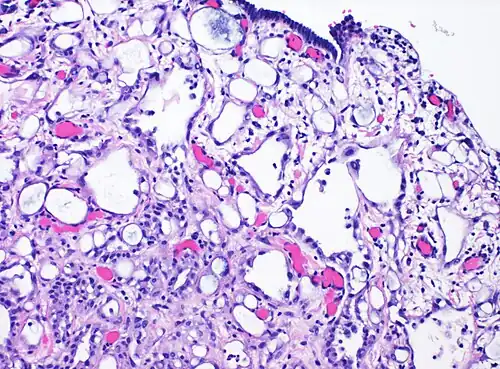

High-magnification micrograph of an adenomatoid tumor. H&E stain.